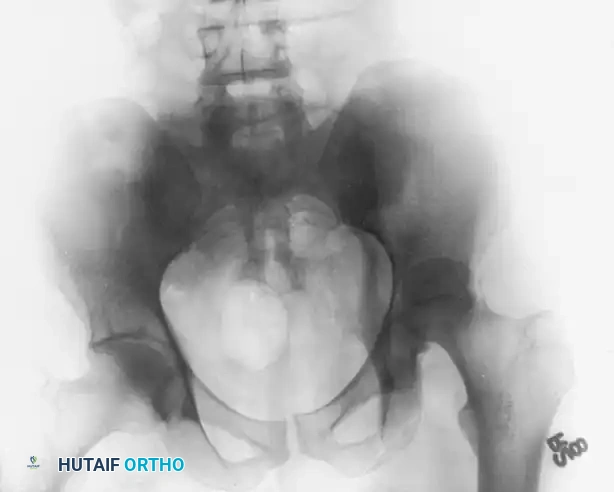

The Anteroposterior (AP) Pelvis View

The AP pelvis view provides a panoramic assessment of the pelvic ring and bilateral acetabula. Inclusion of the opposite, uninjured hip in the radiographic field is essential. This allows the surgeon to evaluate symmetrical contours, account for slight individual anatomical variations, and determine the baseline width of the normal articular cartilage space.

When evaluating the AP view, the surgeon must systematically trace the six fundamental radiographic landmarks of Letournel:

1. The Iliopectineal Line: Represents the anterior column.

2. The Ilioischial Line: Represents the posterior column.

3. The Radiographic Teardrop: Represents the medial wall of the acetabulum. The lateral limb is the inferior aspect of the acetabular fossa, and the medial limb is the quadrilateral surface.

4. The Acetabular Roof (Dome): The superior weight-bearing articular surface.

5. The Anterior Lip (Wall): The anterior margin of the articular surface.

6. The Posterior Lip (Wall): The posterior margin of the articular surface.

Clinical Pearl: The medial clear space between the femoral head and the radiographic teardrop must be meticulously compared between the injured and uninjured hips. Asymmetry or widening on the AP view is a highly sensitive indicator of lateral femoral head subluxation or interposition of intra-articular fragments.